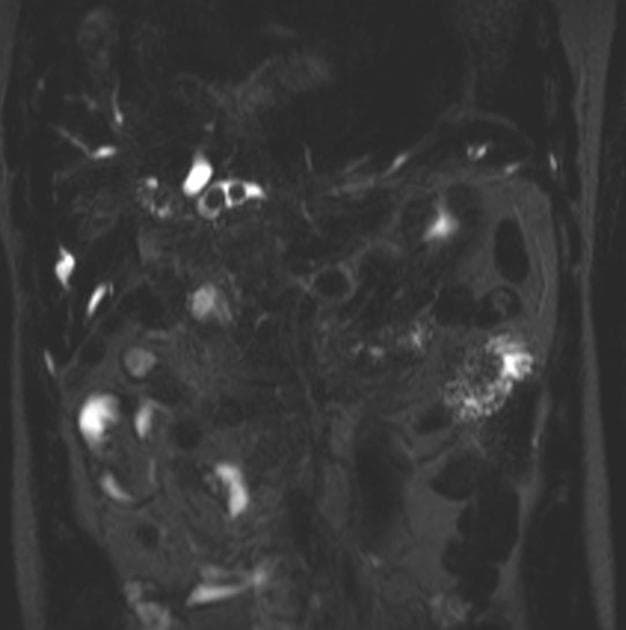

Coronal T2

Nang ống mật chủ - type 4a

Gan: Kích thước to, hình dạng, đường bờ, biên độ và vị trí bình thường. Không thấy nang khu trú hay tổn thương chiếm chỗ (SOL) trong nhu mô gan. Các nhánh đường mật trong gan trung tâm và ngoại vi ở cả hai thùy đều giãn. Không thấy tổn thương lấp đầy giảm tín hiệu trên T2W trong lòng mạch. Chỗ nối các ống gan phải (RHD) và ống gan trái (LHD) tạo thành ống gan chung (CHD).

Túi mật: Phình to, thành dày bình thường. Không thấy tổn thương lấp đầy giảm tín hiệu trên T2W trong lòng túi mật. Ống túi mật giãn và thông nối với ống gan chung (CHD) tạo thành ống mật chủ (CBD). Ống túi mật có vẻ giãn.

Ống mật chung: Cả ống gan chung (CHD) và ống mật chủ (CBD) đều giãn dọc theo toàn bộ chiều dài, với đoạn hẹp đột ngột, nhẵn ở phần xa sau khi tạo thành nhú tá tràng (ampulla). Kích thước tối đa của ống mật chung là 14,4 mm. Không thấy tổn thương lấp đầy giảm tín hiệu trên T2W trong lòng ống.

Ống tụy: Ống tụy chính (MPD) và ống tụy phụ hợp lại với nhau rồi cùng nhập vào ống mật chủ (CBD) tạo thành nhú tá tràng (ampulla). MPD có vẻ giãn.

Nang ống mật chủ - type 4a (choledochal cyst - type 4a)

- "Nang ống mật chủ type 4a bao gồm tình trạng giãn cả ống mật trong gan và ngoài gan."